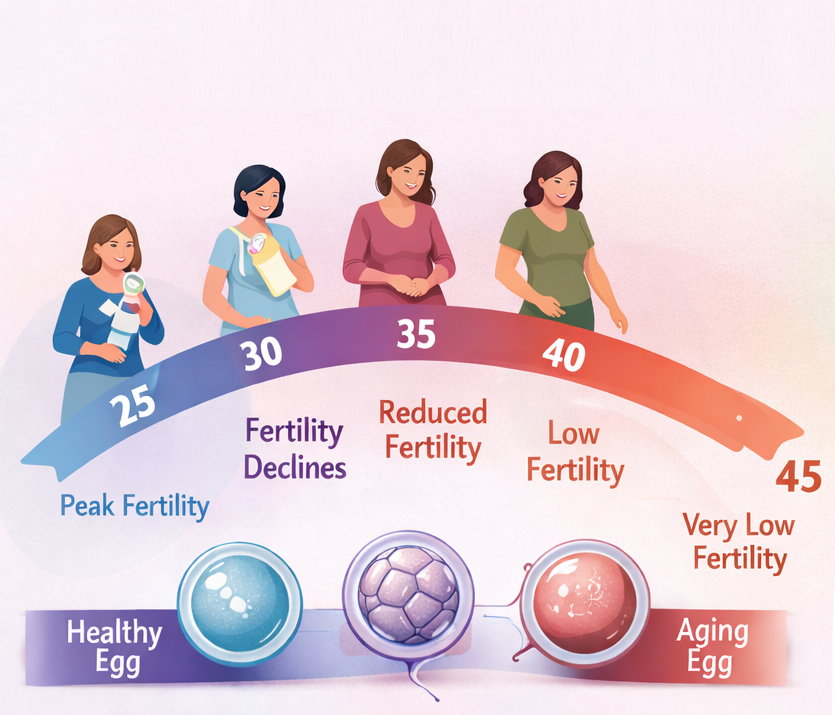

Lifestyle Tips to Improve Fertility?

What Are the Causes of Female Infertility? Symptoms, Diagnosis & Treatment

Female infertility causes are one of the most common concerns faced by couples trying to conceive. Today, nearly 1 in…